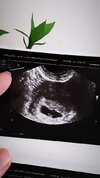

Ja po wizycie 6+1 z USG więc ciąża młodsza niż by to wyglądało z miesiączki. Serduszko biło 138 uderzeń na godzinę. Jeżeli z pulsem się mi sprawdzi to będzie chlopak ale to tylko wróżenie 😂